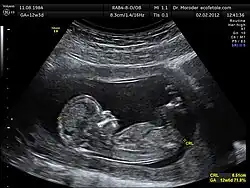

Comprimento cabeça-nádega

Comprimento cabeça-nádega (CCN) é a medida do comprimento de embriões e fetos humanos desde o topo da cabeça (céfalo) até a parte inferior das nádegas. Geralmente é determinado a partir de imagens de ultrassom e pode ser usado para estimar a idade gestacional.